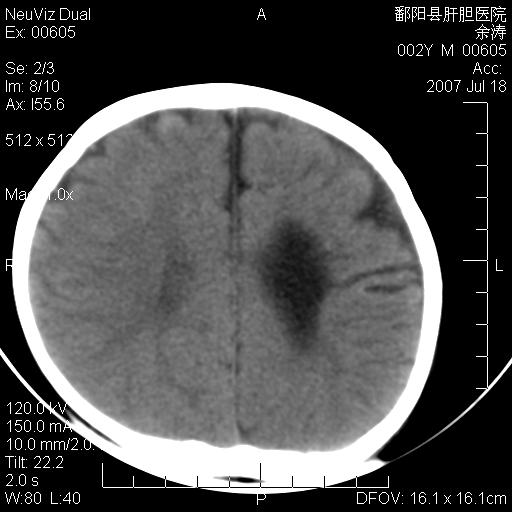

男性 2岁:平时智力障碍。外伤后行颅脑平扫。

左颞叶“萎缩”,可见不规则高密度影,并左侧室扩大,呈负占位效应...支持考虑先天发育异常(血管发育畸形)可能性大,建议结合进一步检查了解。

左颞叶“萎缩”其内可见不规则点条状高密度影,并左侧室扩大,考虑颅面血管瘤病

脑裂畸形;左侧脑脑萎缩;透明隔囊肿;血管畸形?

开唇型脑裂畸形

左侧颞顶叶钙化灶,其内有小片状低密度影 边缘清晰。与之相邻的脑沟增宽增深 ,左侧侧脑室体部牵拉扩大。考虑左颞顶软化灶并局限性脑萎缩。透明隔间腔。

该病人应该还有胼胝体发育不全